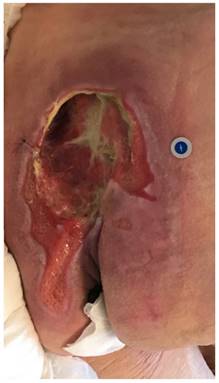

Figure 2

Ulcer in sacrum area

Int J Med Sci Image

The study included patients diagnosed with a chronic wound of pressure ulcer-related etiology. The inclusion criteria were: (1) stage II, III or IV according to the EPUAP/NPUAP classification system for pressure ulcer [12], (2) wound area at least 0.5 cm2 and not more than 50 cm2, (3) duration of the condition between min. 6 to max. 24 months and (4) location of pressure ulcers in the sacrum and pelvis (Figure 2). The exclusion criteria were: (1) a clinically detectable wound infection (critical bacterial colonization confirmed by wound swab and bacteriological examination, foul odor, increased pain and inflammation in the tissue around the ulcer, lympho-flow and significant serous effusion), (2) use of drugs, such as corticosteroids, anticoagulants, opiates, antibiotics (3) use of special active dressings such as hydrocolloids, hydrogels, alginate, with the addition of metallic silver or any other type of therapeutic procedures different from those planned and used in this study, (4) non-compliance with ulcer management recommendations, (5) pregnancy, (6) ankle-brachial pressure index (ABPI) < 0.8, (7) diabetes (HbA1C > 7%), (8) systemic sclerosis, collagenases, psoriasis and other autoimmune diseases, (9) neoplastic disease, (10) allergic reactions (11) diagnosed mental illness, alcoholism or other addictions.